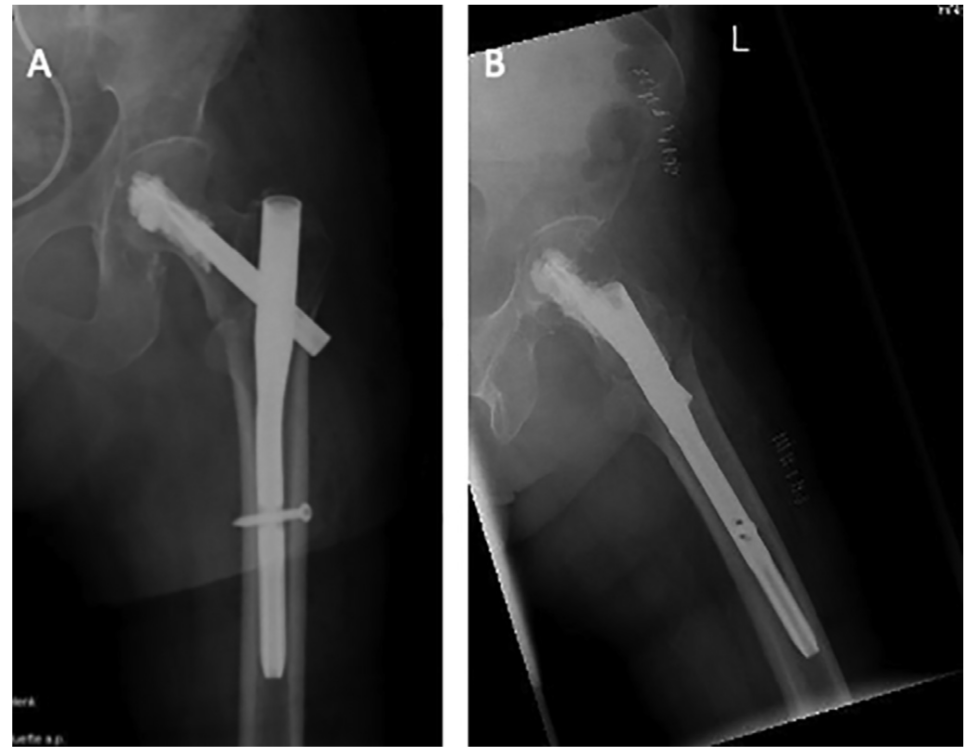

股骨近端骨折是老龄患者最常见的骨折之一,其中50%累及转子周围区域。老龄患者骨质疏松,PFNA内固定术后早期功能锻炼可能导致螺钉切割、内固定失效等并发症,而早期功能锻炼对患者功能恢复至关重要。因此,有学者研究了骨水泥加强的PFNA,以评估能否增加老龄患者患肢早期的负重能力。

粗隆间骨折髓内固定失效,需要注意这一点!